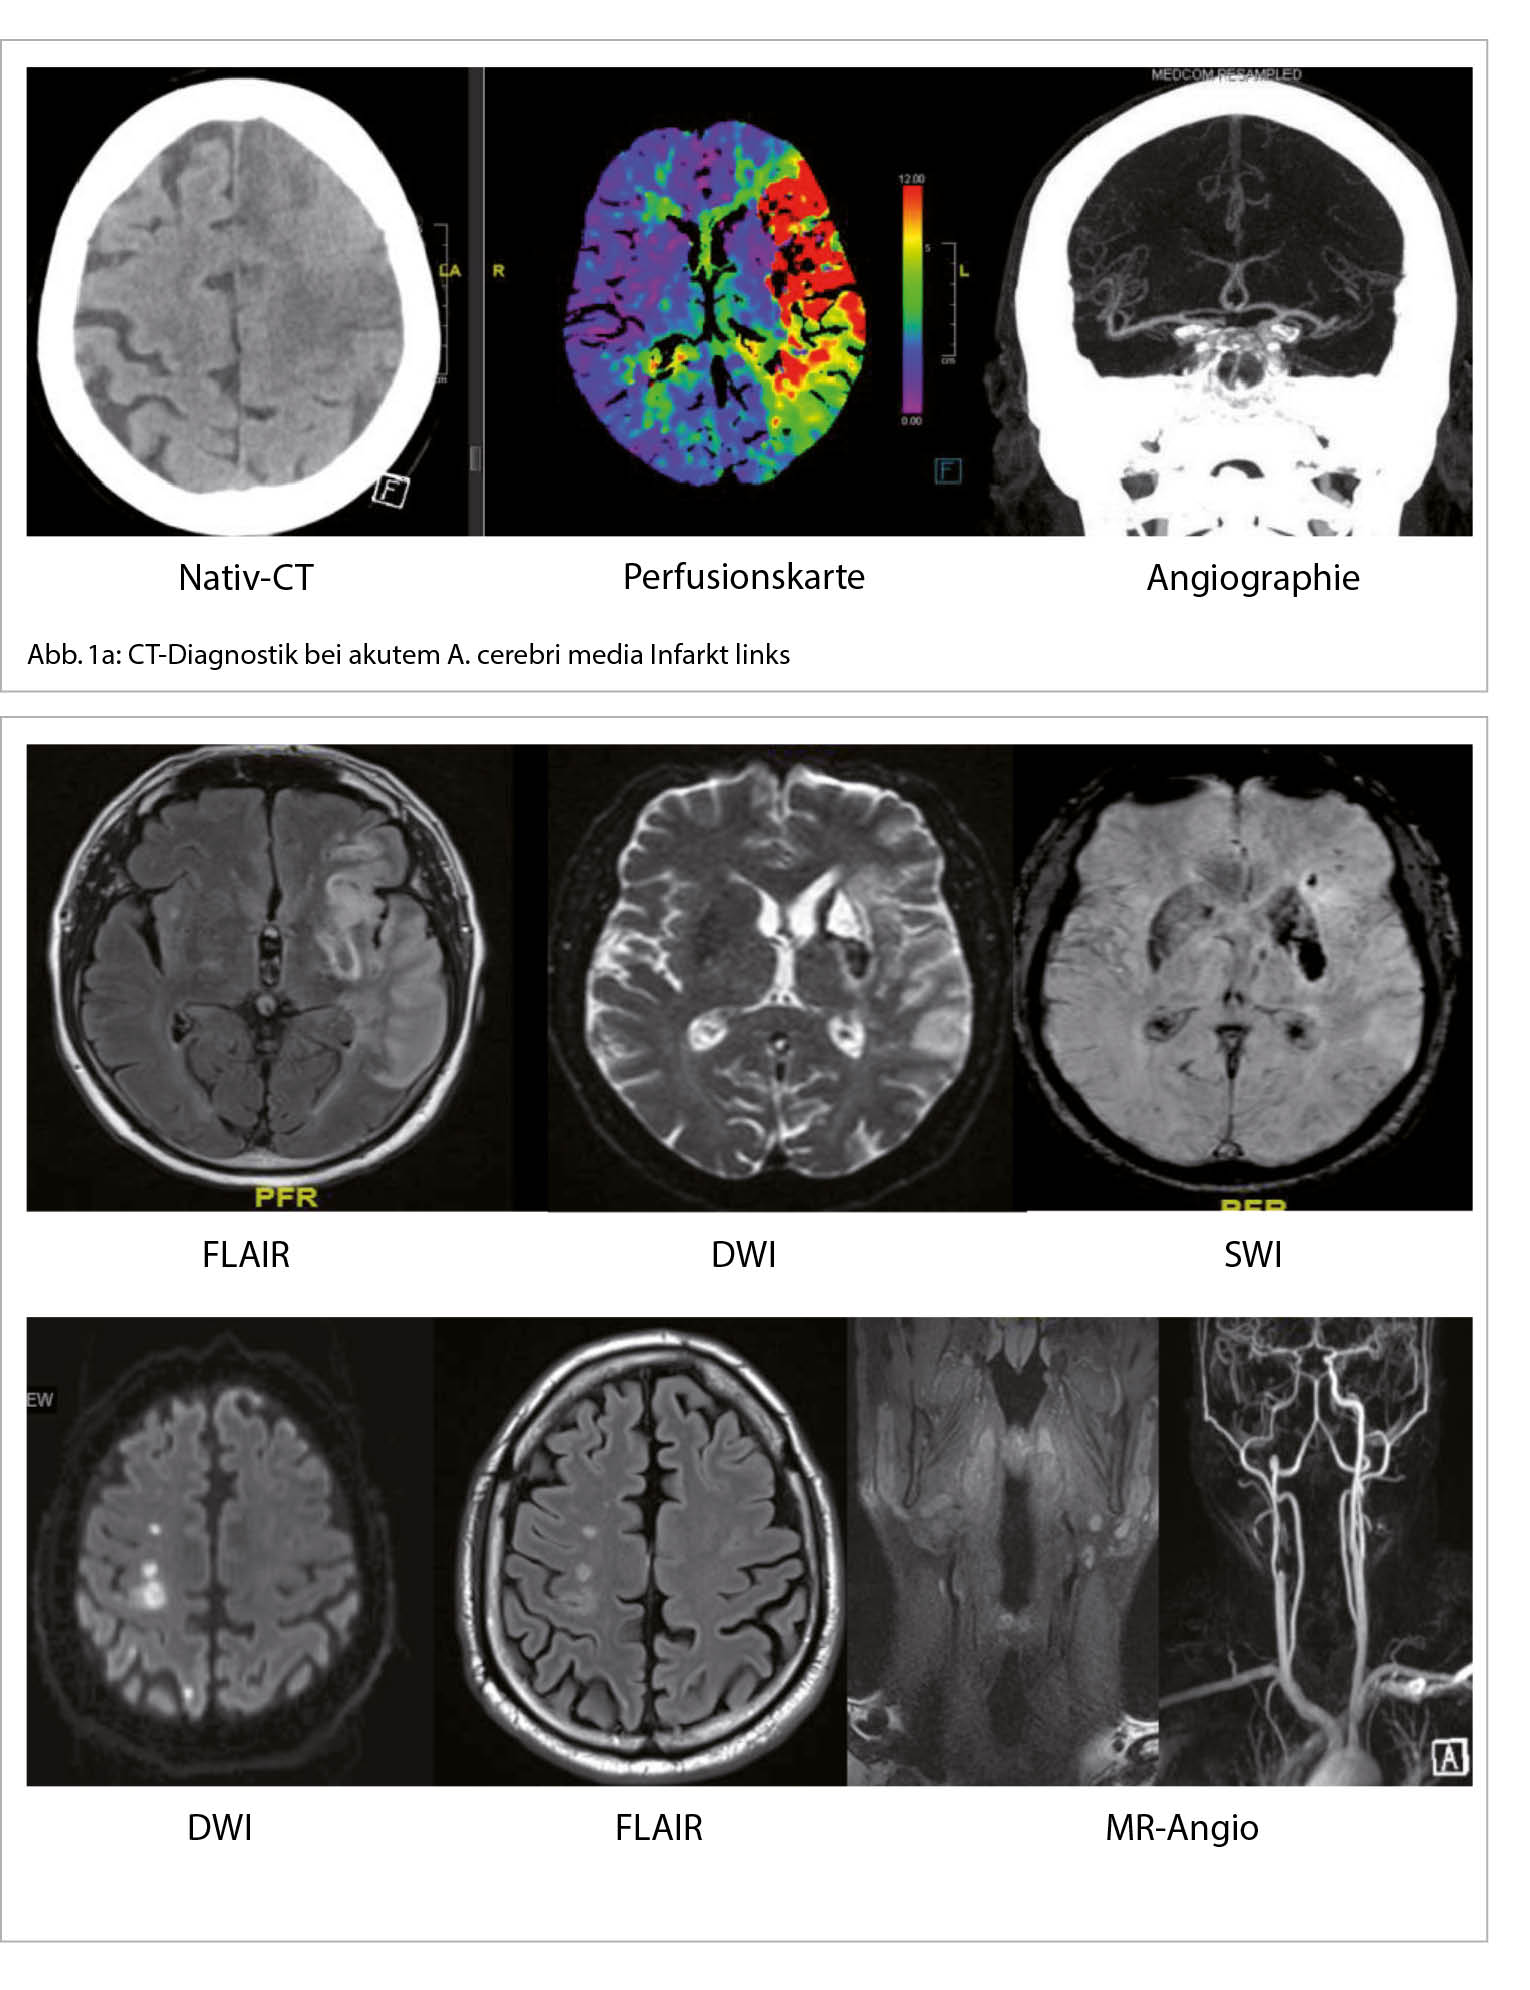

Wenn nach der ersten anamnestischen und klinischen Beurteilung die klinische Vermutung auf einen akuten Hirnschlag vorliegt, ist im Hinblick auf eine revaskularisierende Therapie der Ausschluss einer intrakraniellen Blutung sowie einer nicht vaskulären Pathologie wichtig. Gleichzeitig beginnt auch die Abklärung der Schlaganfall-Ätiologie. Dazu ist eine erste Bildgebung mittels CT- oder MRI-Untersuchung notwendig. Die Entscheidung zwischen CT oder MRI in der akuten Phase ist stark von Klinikressourcen und Zeit-Effizienz des entsprechenden Behandlungsprotokolls abhängig. Eine Vorgehensweise mit CT-Scan beinhaltet erst ein natives CT (ohne Kontrastmittelgabe), um eine intrakranielle Blutung als Ätiologie des Ereignisses auszuschliessen. Dafür ist das CT-Scan sehr zeiteffizient und präzise. Danach folgt die Kontrastmittel-Gabe mit CT-Angiographie, um den Status der hirnversorgenden Gefässe zu beurteilen und einen potentiellen Gefässverschluss zu diagnostizieren. Zuletzt dient die Perfusions-Untersuchung dazu, das Volumen des möglichen rettbaren Hirngewebes zu bestimmen und eine revaskularisierende Therapie zu indizieren (Abb. 1a). Eine MRI-Erstbildgebung ist sensitiver für die Hirnschlagdiagnose, da sehr früh das ischämische Gewebe erkannt werden kann. Die kernspintomographische Vorgehensweise beinhaltet diffusionsgewichtete (DWI) und suszeptibilitätsgewichtete (SWI) Aufnahme-Protokolle, die jeweils zwischen einem ischämischen und hämorrhagischen Ereignis differenzieren und eine genaue Lokalisation der Läsion geben können. Ergänzend dazu geben die ADC und FLAIR Protokolle hilfreiche Informationen bezüglich des zeitlichen Verlaufs der Läsion. Der Gefäss-Status kann im Hinblick auf signifikante Stenosen oder anderen Gefässerkrankungen wie Dissektionen, Vaskulitiden etc. mittels einer MR-Angiographie beurteilt werden (Abb. 1b, 2) (2, 3).